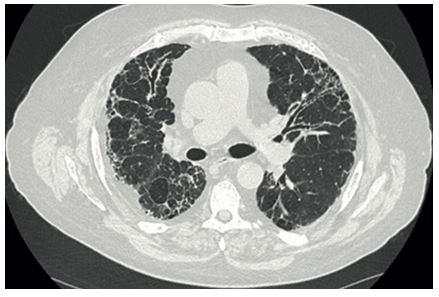

C. Fibrose pulmonaire (VAA-MPO)

Chez les patients avec VAA-MPO, une fibrose pulmonaire diffuse peut être observée (Figure 6). Elle peut se présenter :

- soit comme une atteinte isolée sans signes de vascularite systémique,

- soit comme une complication survenant au décours d’un épisode d’HIA.